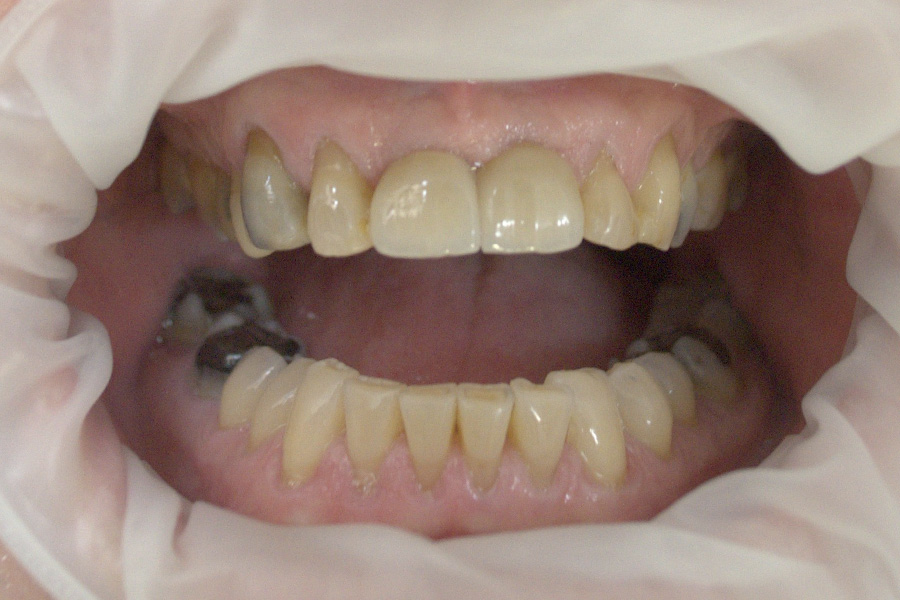

Phil was wearing a removable partial denture for many years.

As he lost some more teeth the pasrtial denture became less stable. Chris finally decided to have dental implants his missing teeth.

Two implants were utilised to support a bridge where there were three missing teeth in a row. His existing natural teeth received crowns and veneers as reinforcements and also to match the highly esthetic implant crowns and bridges.